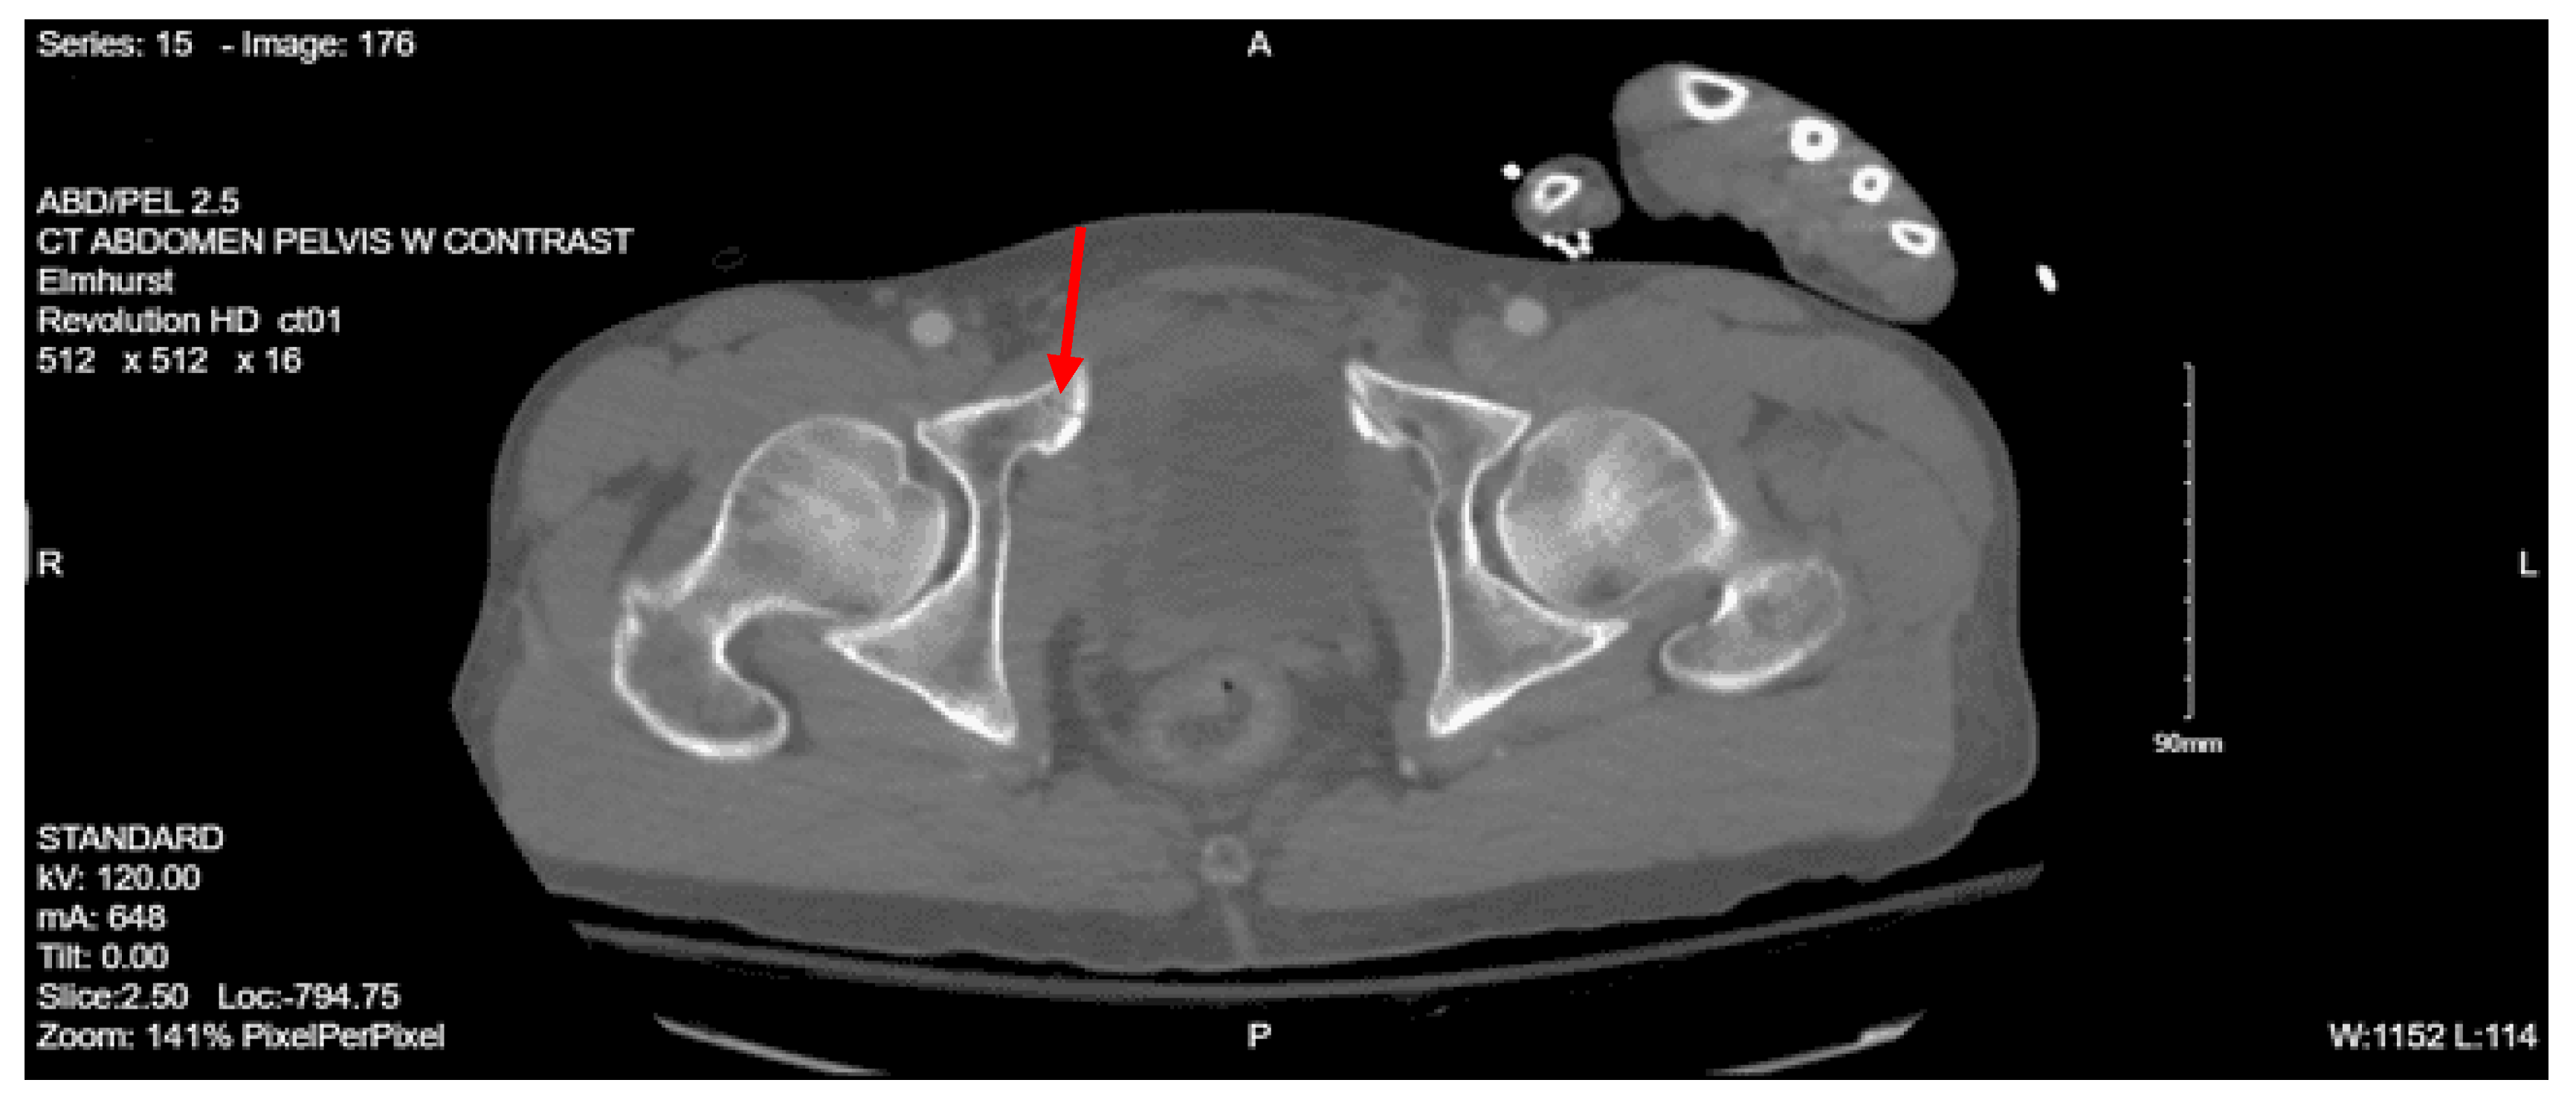

Imaging as shown in Figure 17 and Figure 18:

CT abdomen pelvis with contrast: Acute nondisplaced bilateral sacral alar fractures with extension into the sacroiliac joint on the right and probable involvement of the right S3 neural foramen. Amorphous hematoma in the medial left gluteal musculature and subcutaneous fat measuring approximately 3.3 x 6.6 x 7.7 cm. No visceral organ injury.